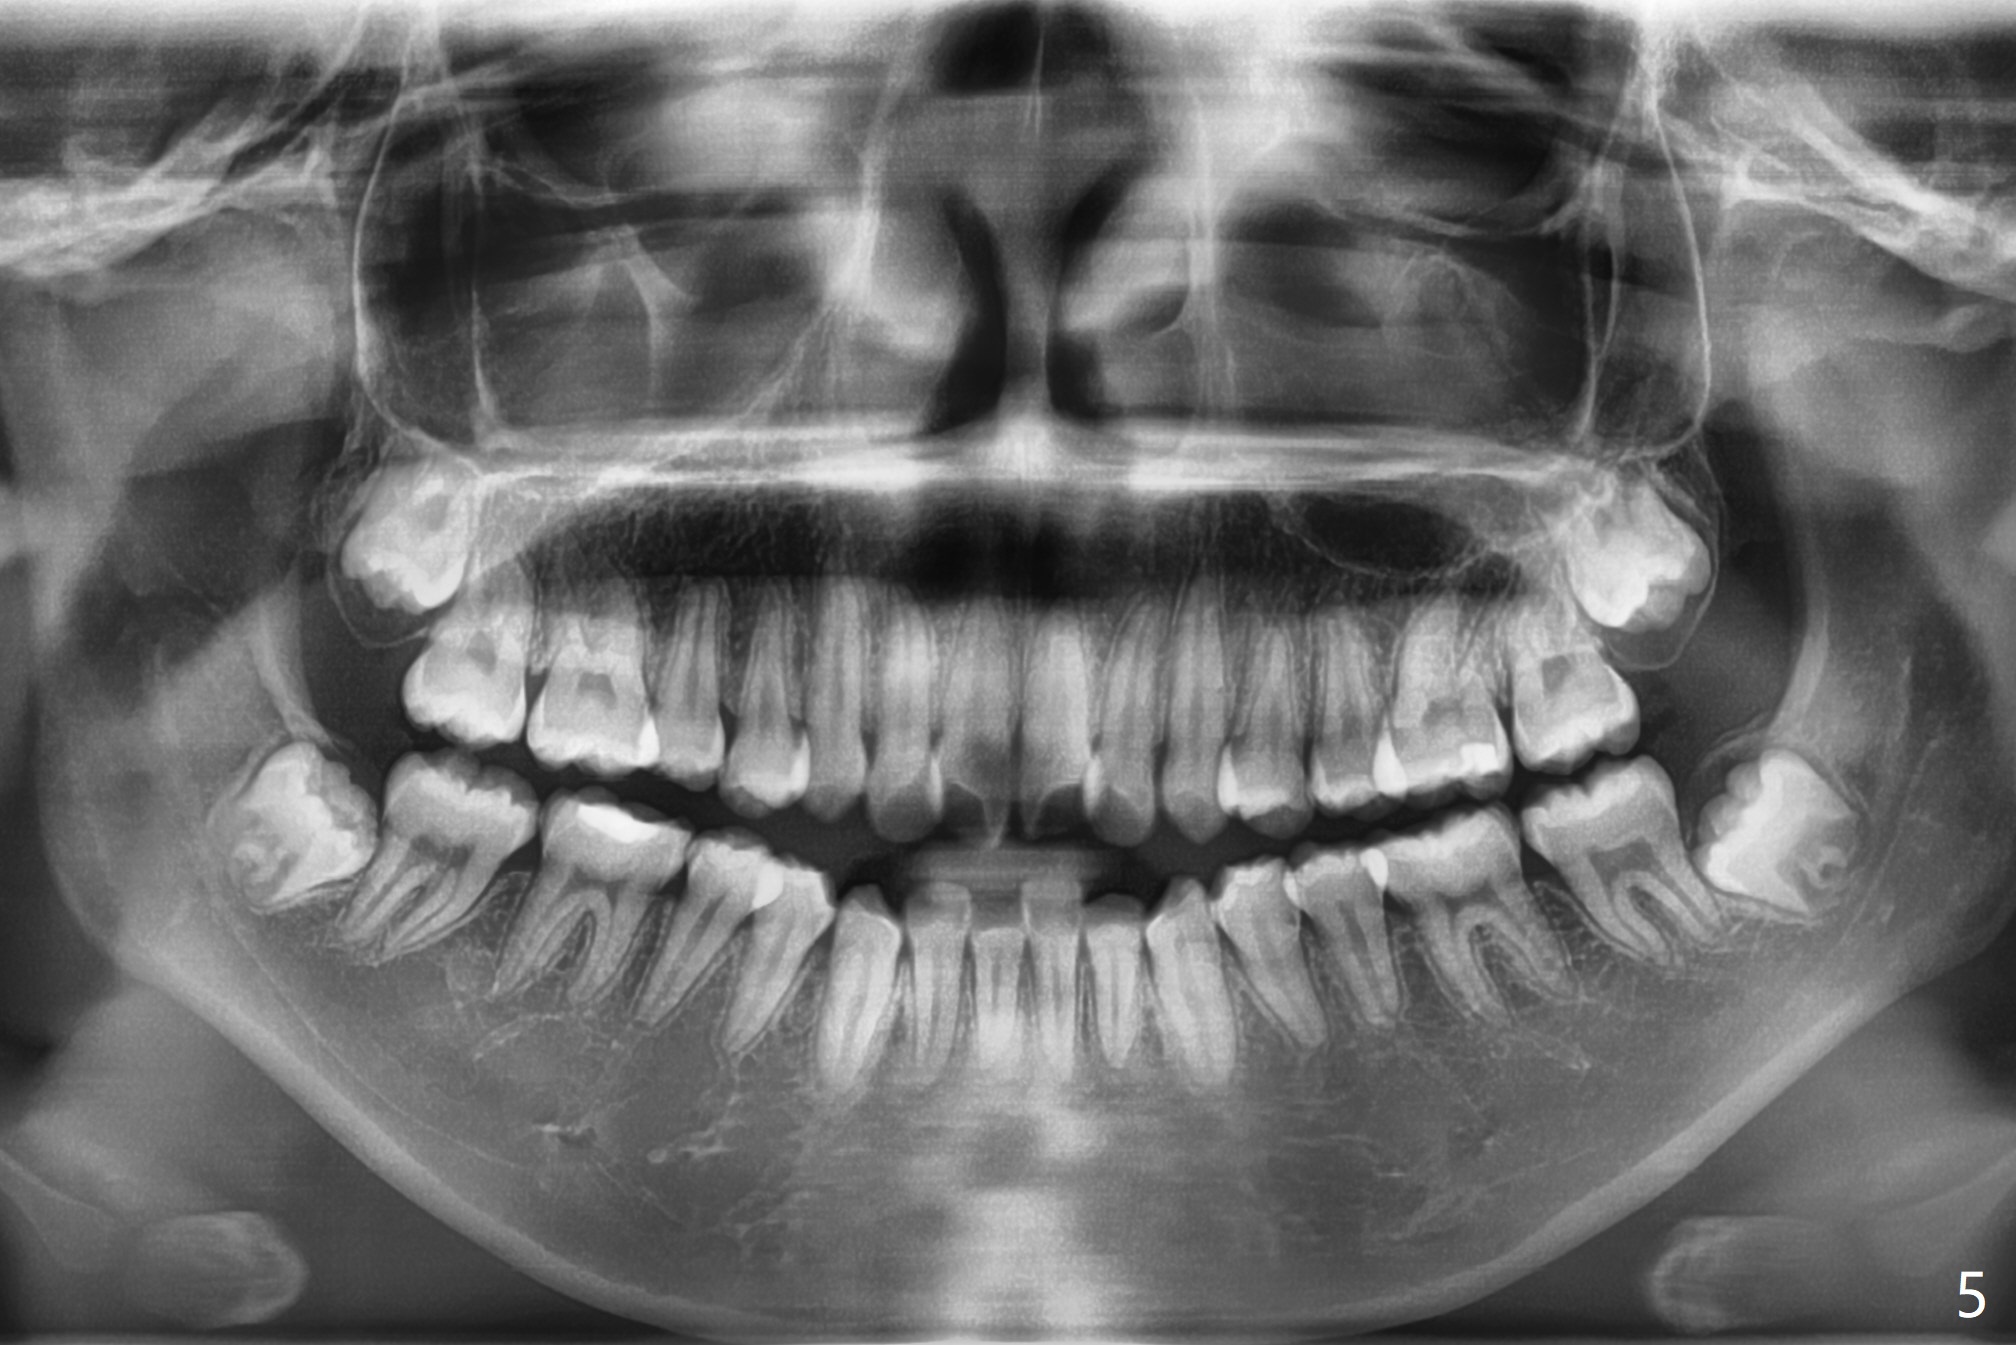

A 14-year-old woman has convex facial profile (Fig.1-4) with the upper midline shifted to the left (Fig.2). Since the roots of the 1st bicuspids are short (Fig.5), extraction should be easy. U3 will be retracted distal early with intention to correct the upper midline. With Class I occlusion at the canines and the 1st molars and good initial interdigitation (Fig.6-11), orthodontic treatment should be rewarding. Because of severe crowding (tight contact, Fig.12,13), place separators after extraction and place bands and brackets a few days later. Cephalometric analysis (Fig.14) shows that SNB is greater than SNA (82.4 vs. 81.8 degree); after extraction, retract the lower anterior teeth prior to the upper ones. It is easy to place separators after extraction (Fig.16,17).